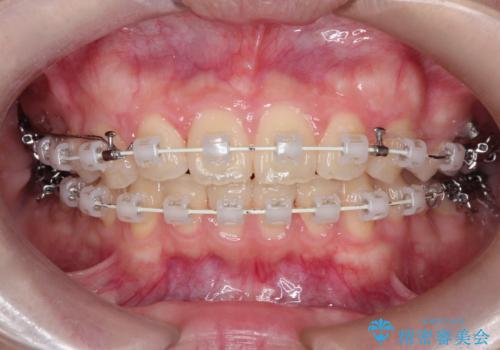

【ワイヤー矯正】前歯の真ん中を合わせたい。

上と下の前歯がずれているため、抜歯を行い前歯の真ん中を合わせる治療計画を立ててワイヤー矯正にて治療を行いました。

途中、矯正用のアンカースクリューを使うことで、最終的にきれいに前歯の真ん中を合わせることができました。